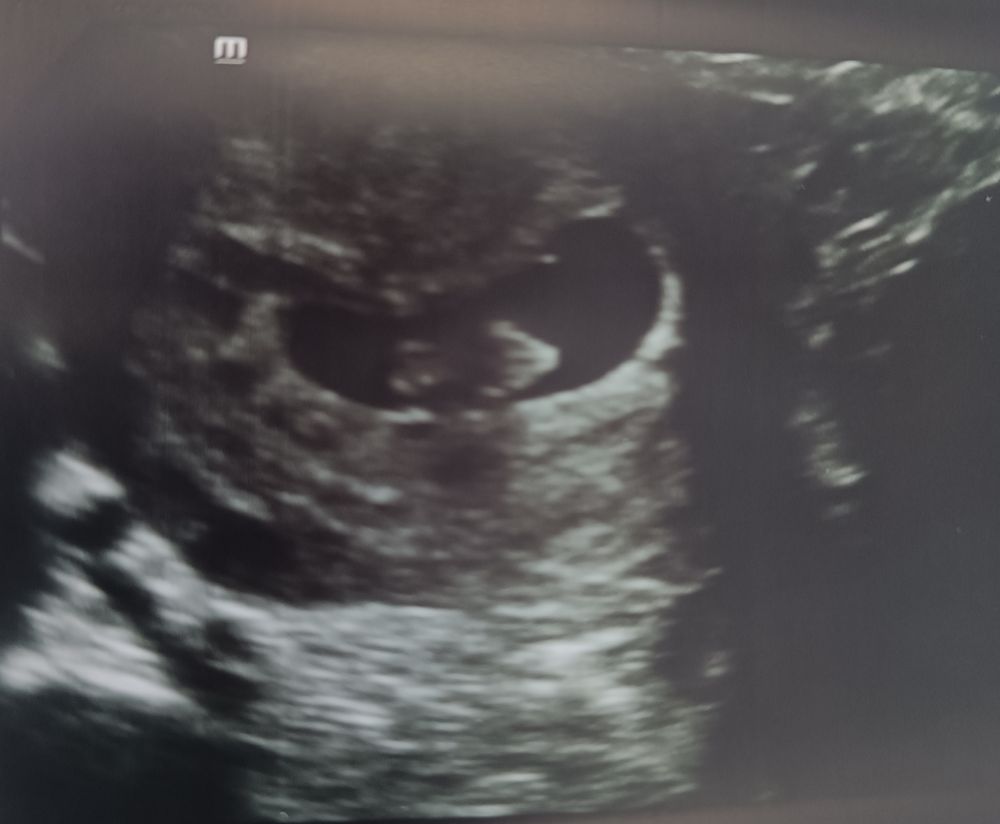

Светик,

Смотрите, сверху вниз. 5 недель, 6 недель, 8 недель. Как тут не увидеть?))